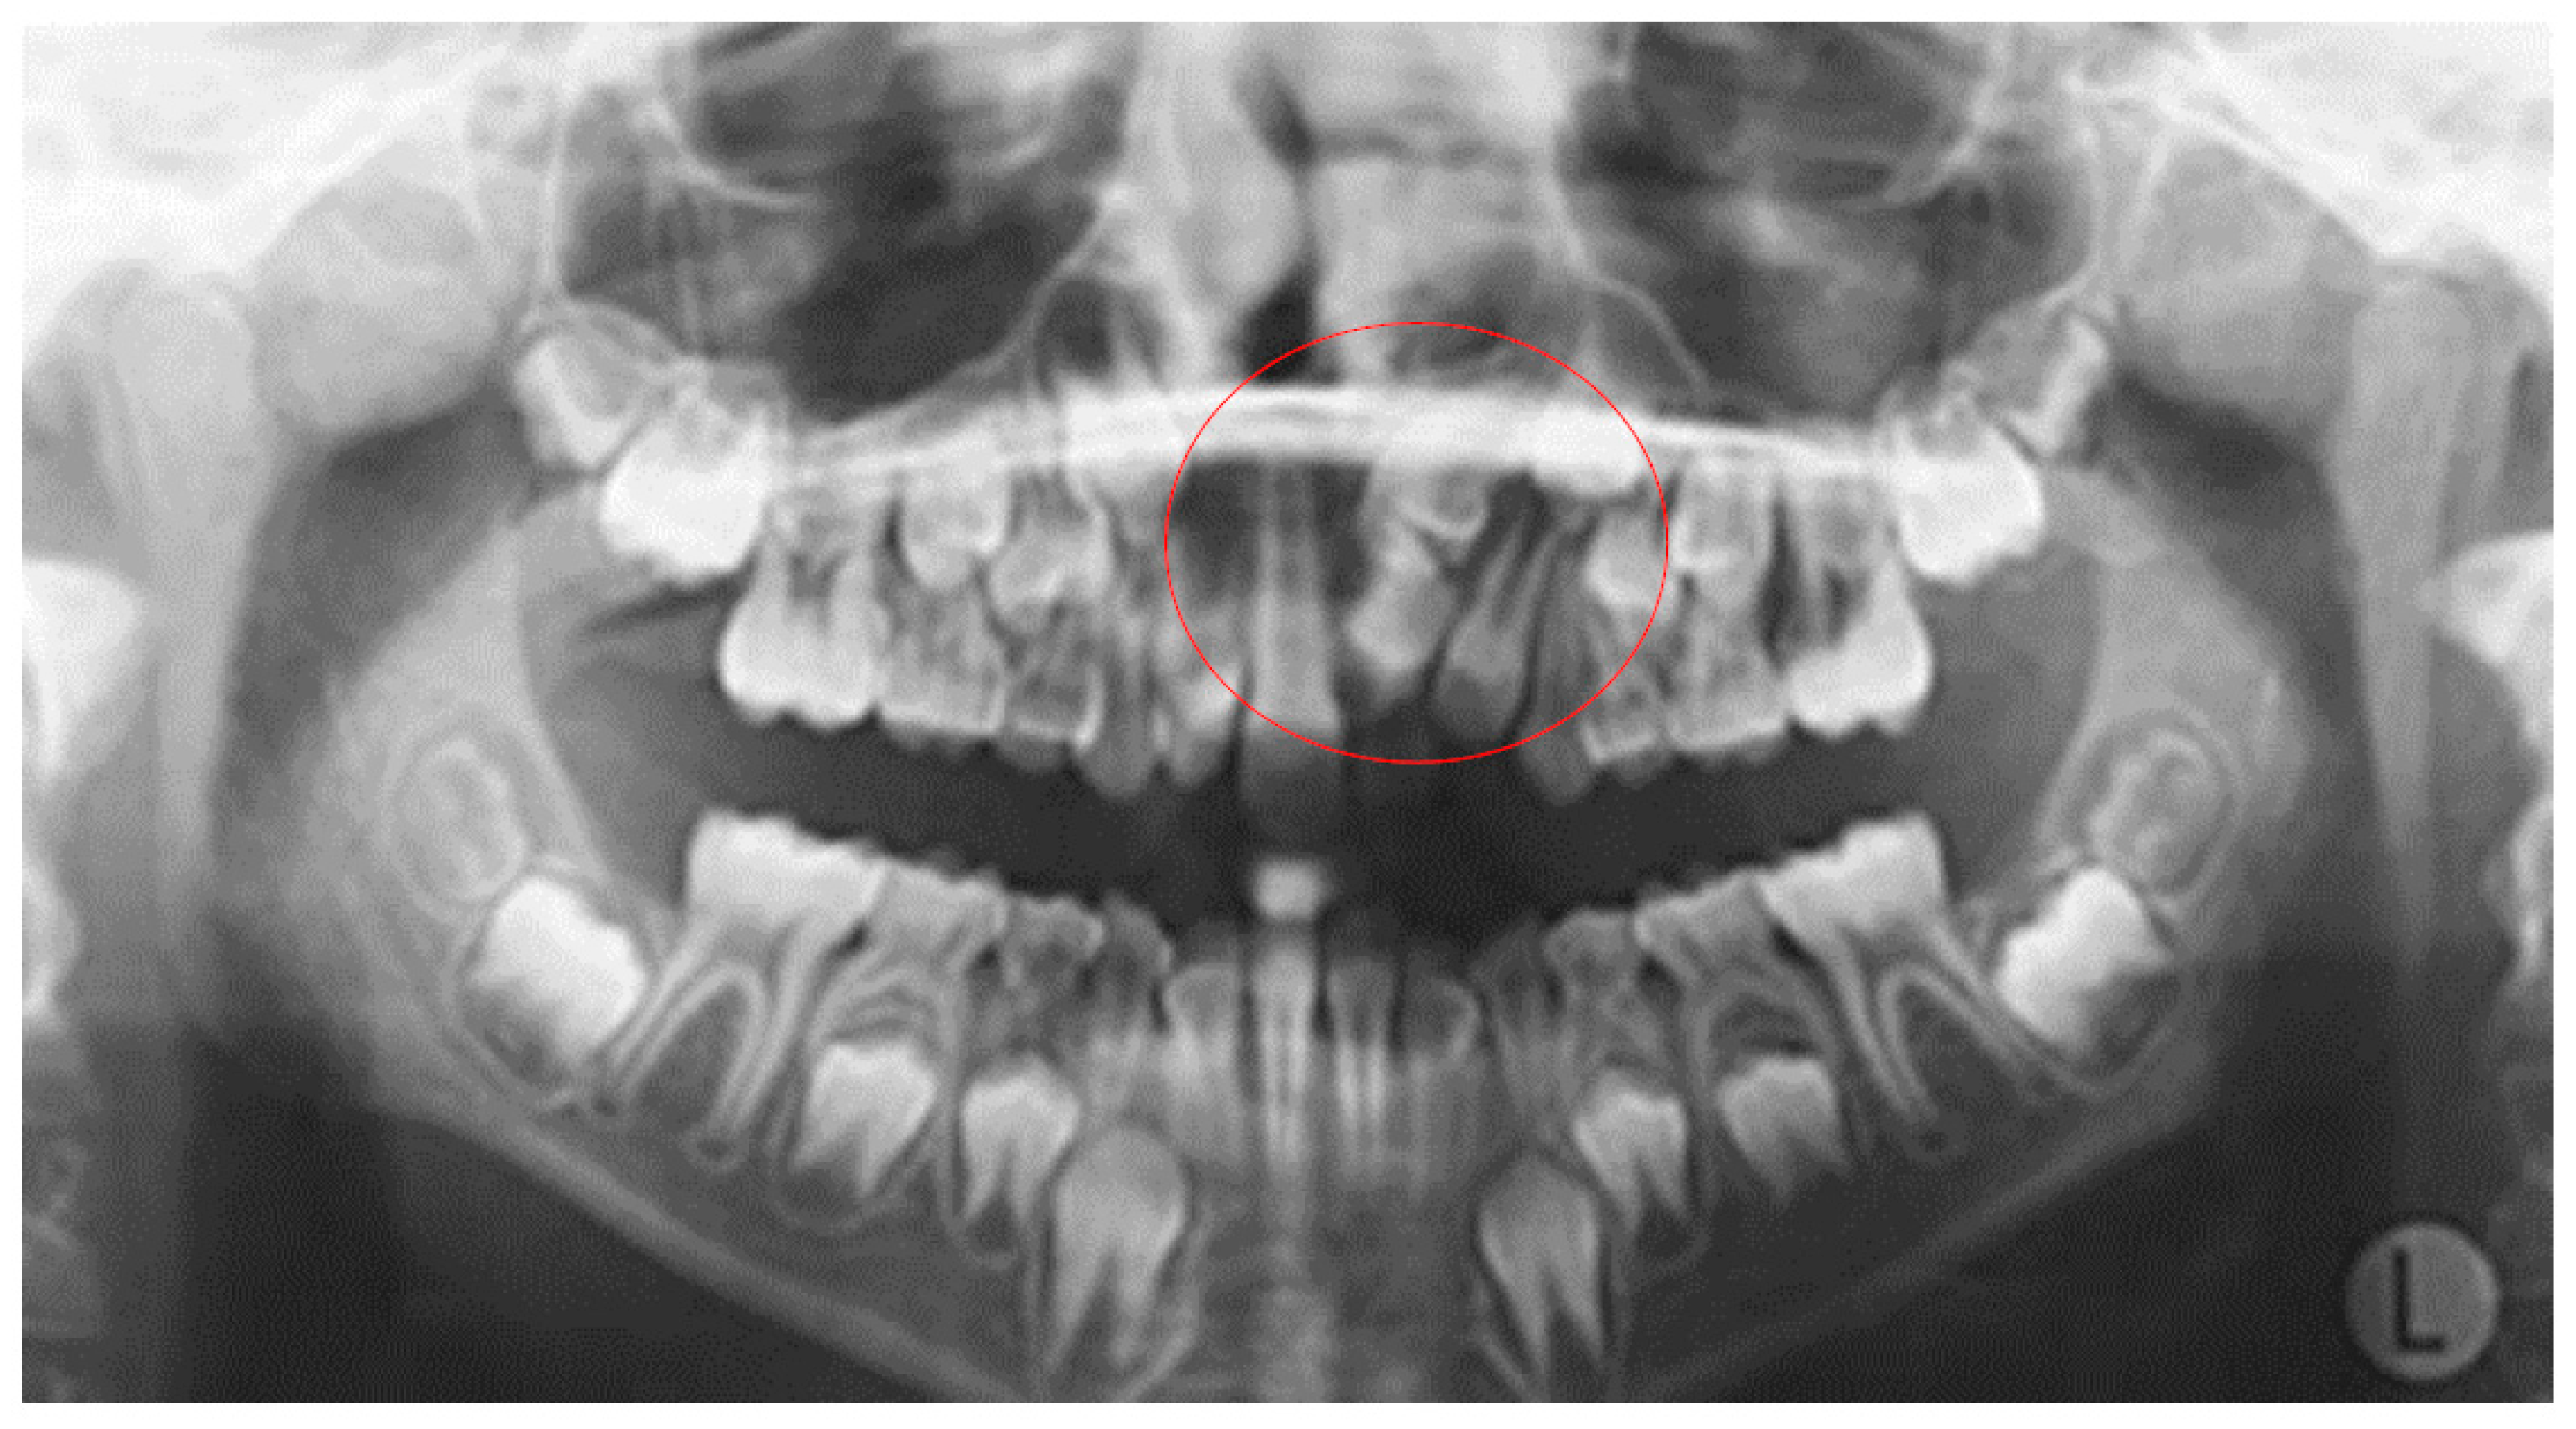

As far as the etiology of impaction is concerned, 205 patients presented one factor responsible for impaction, while 7 presented two. Table 2 shows the ectopic eruption path as the most frequent factor that was reported in 5.29% of total patients examined and mostly reported in maxillary canines. The next most common etiology was the loss of space in the arch (2.50%), followed by the ankylosis of deciduous teeth (1.71%). Concerning the rest of the causative factors, supernumerary teeth other than deciduous were observed in 1.29% of the patients, while the mesiodens was the most frequent supernumerary permanent tooth. In total, 1.21% of the sample presented tumors such as odontoma and osteoma, more often in association with maxillary central incisors. Supernumerary deciduous teeth affected 0.86% of the patients examined, while the ankylosis of permanent teeth was presented in 0.79 of the cases. The maxillary second premolars were the most frequently impacted teeth due to ankylosis. The least common etiology of impaction proved to be the primary failure of eruption, with 3 reported cases out of 212 patients, that following the radiographic examination were all confirmed by genetic tests. Panoramic radiographs indicated for some local etiological factors are presented below (Figure 1, Figure 2, Figure 3 and Figure 4).

Figure 2. Impacted first mandibular molars.